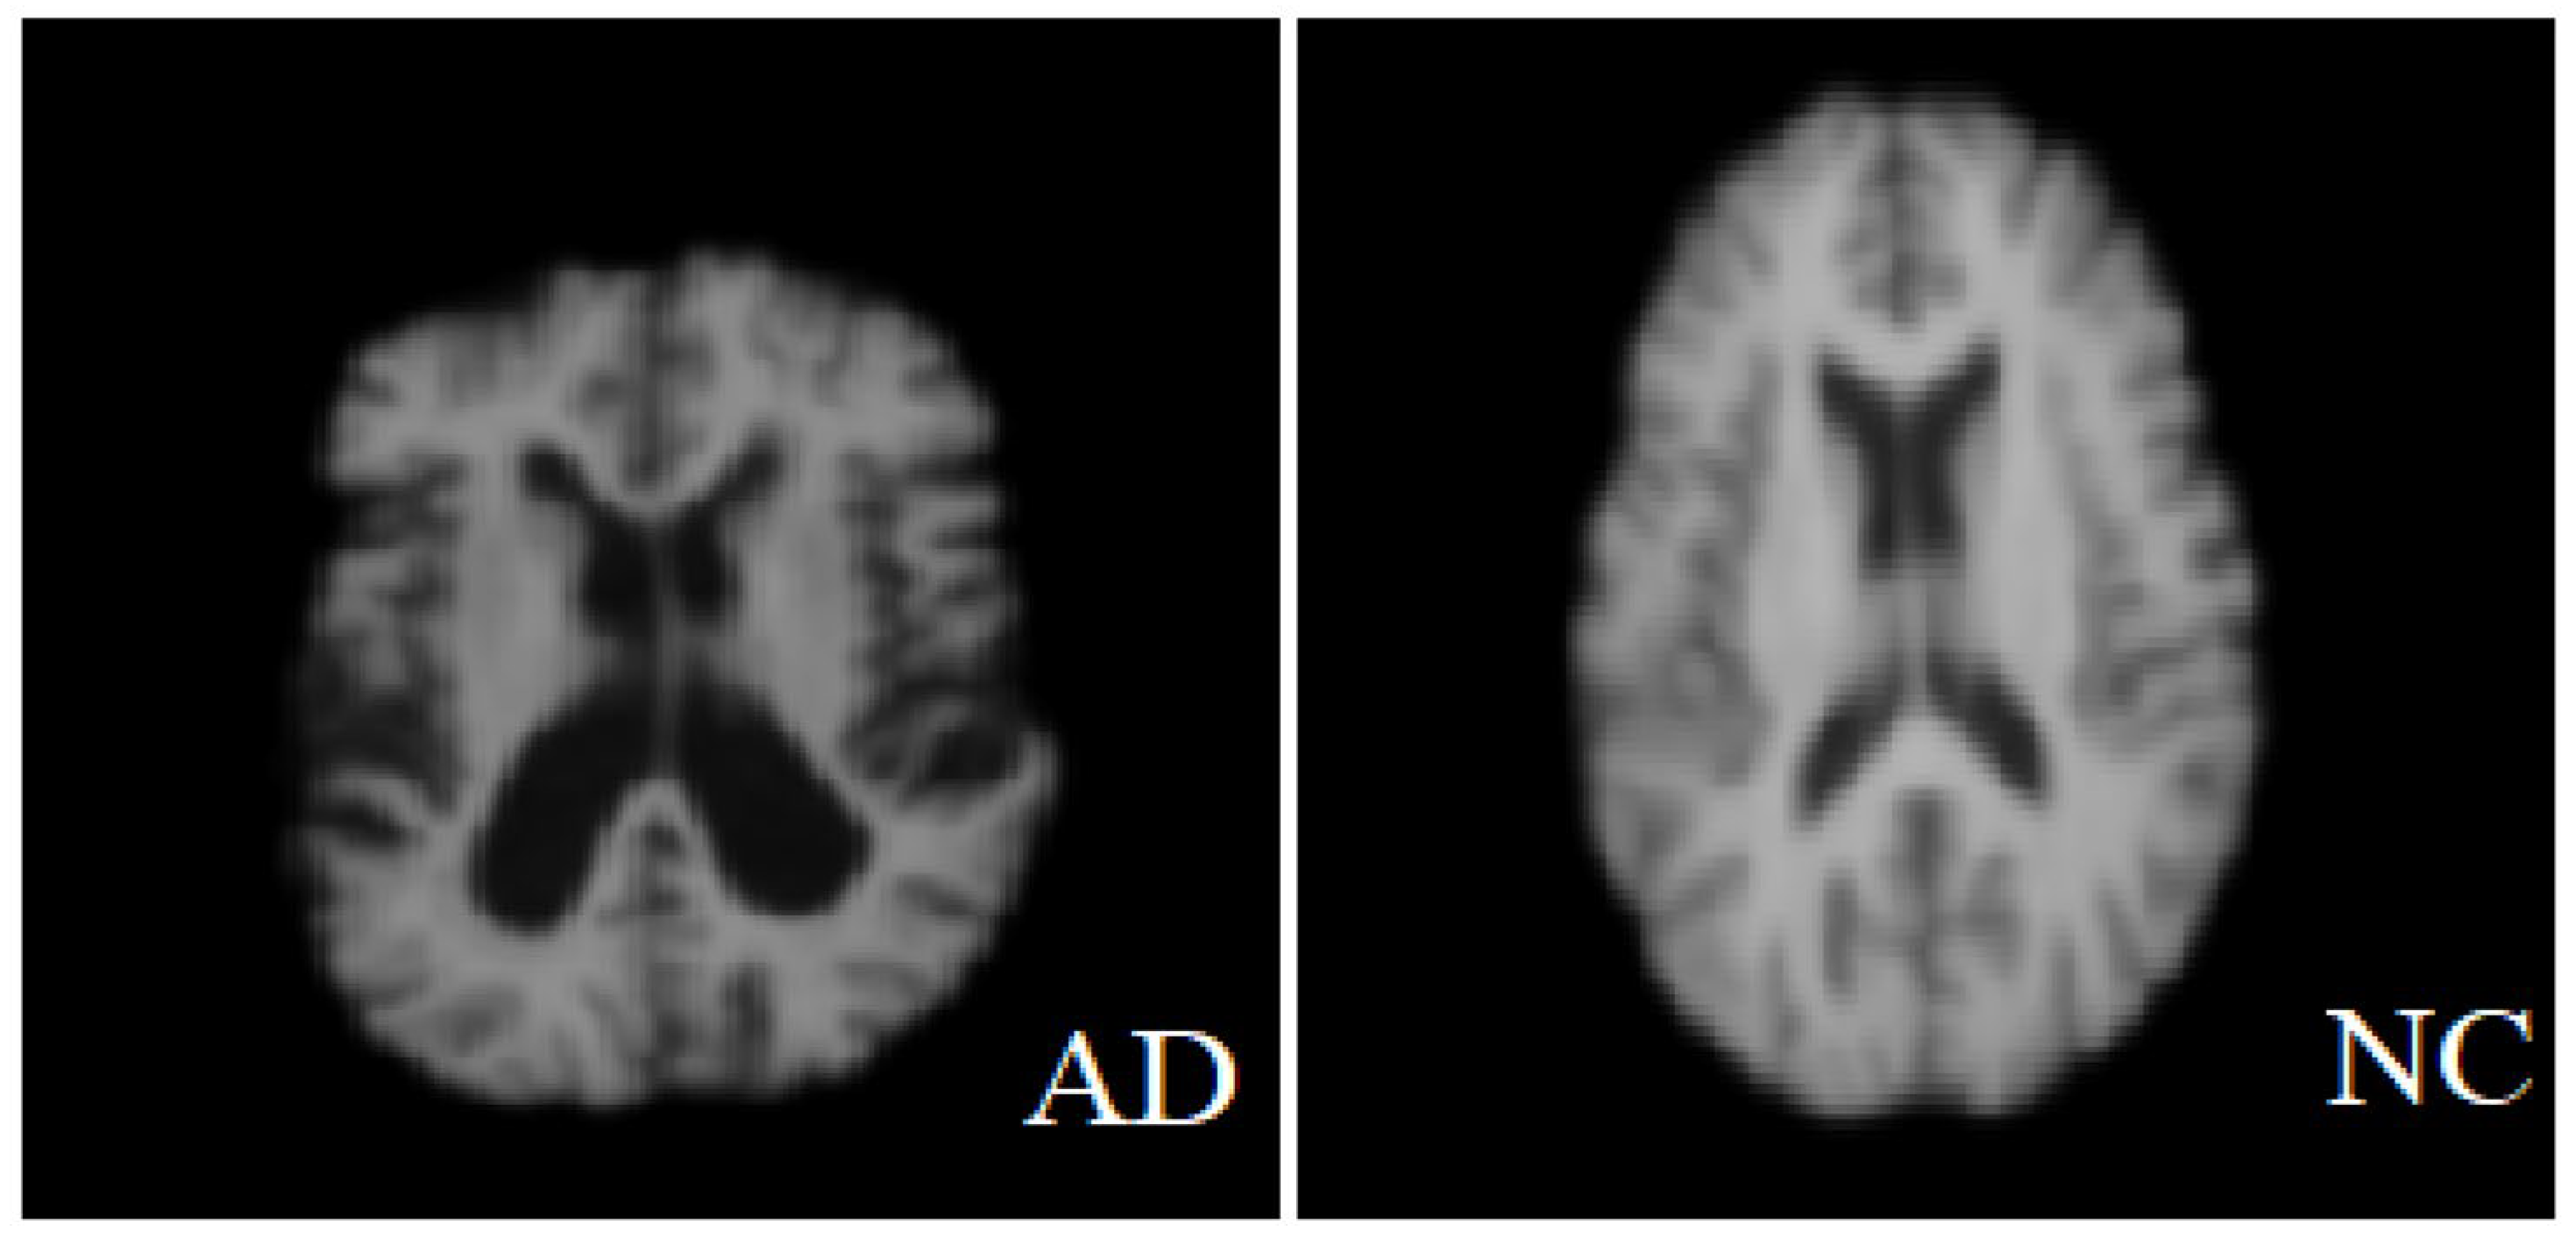

The MRI images used in this study were obtained from two publicly available datasets: the Alzheimer’s Disease Neuroimaging Initiative (ADNI) and minimal interval resonance imaging Alzheimer’s disease (MIRIAD). Official permission was secured for using the ADNI dataset, and no external image sources were used. The ADNI dataset is designed to monitor the early progression of Alzheimer’s disease and includes MRI scans with 128 sagittal slices, typically formatted as 256 × 256 matrices. It comprises data from 741 participants, including 314 AD patients and 427 normal controls subjects. The MIRIAD dataset includes MRI images of 46 AD patients and 23 normal controls, scanned at time points between 2 weeks and 2 years [40,41]. In this study, all image processing, model training, and evaluation were performed exclusively on sagittal slices due to their consistency and suitability for analysis. Axial slices were used solely for visualization purposes in Figure 2, given their higher display quality. The figure illustrates examples of benign and malignant images from both ADNI and MRTIAD datasets, helping to visually distinguish between the two diagnostic categories. Table 2 groups the samples by dataset and class (Alzheimer’s disease—AD and control—NC), showing the total number of samples for each category, and then shows their distribution into training (70%) and test (30%) sets.

Figure 2.

Two examples of malignant and benign Alzheimer’s images [42].